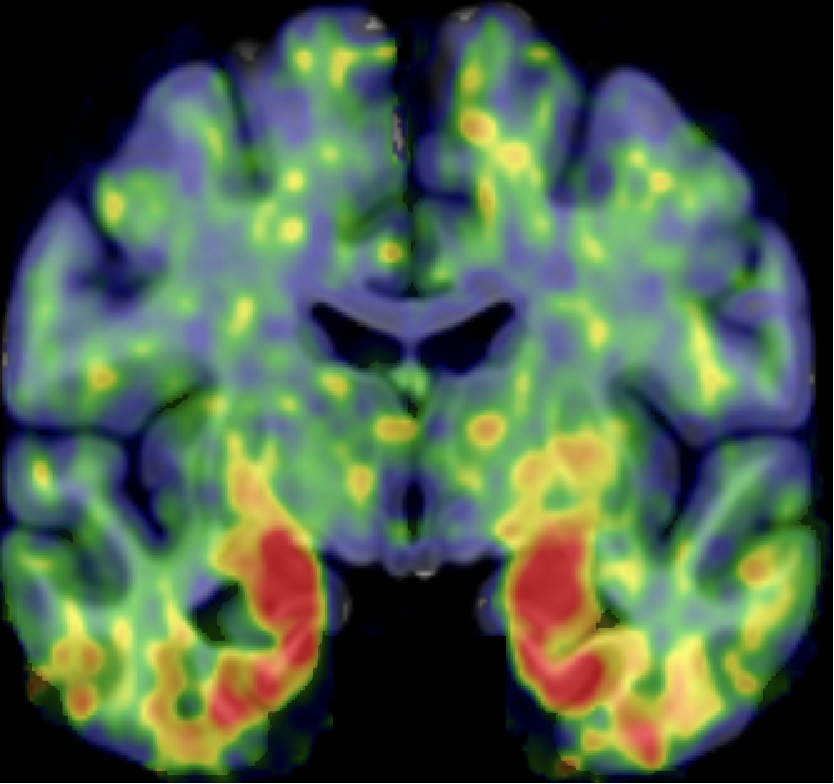

【D期(晚期)】

• 表现:核心1阳性,新皮层有大量Tau沉积

• 意味着:病变广泛,全脑受累